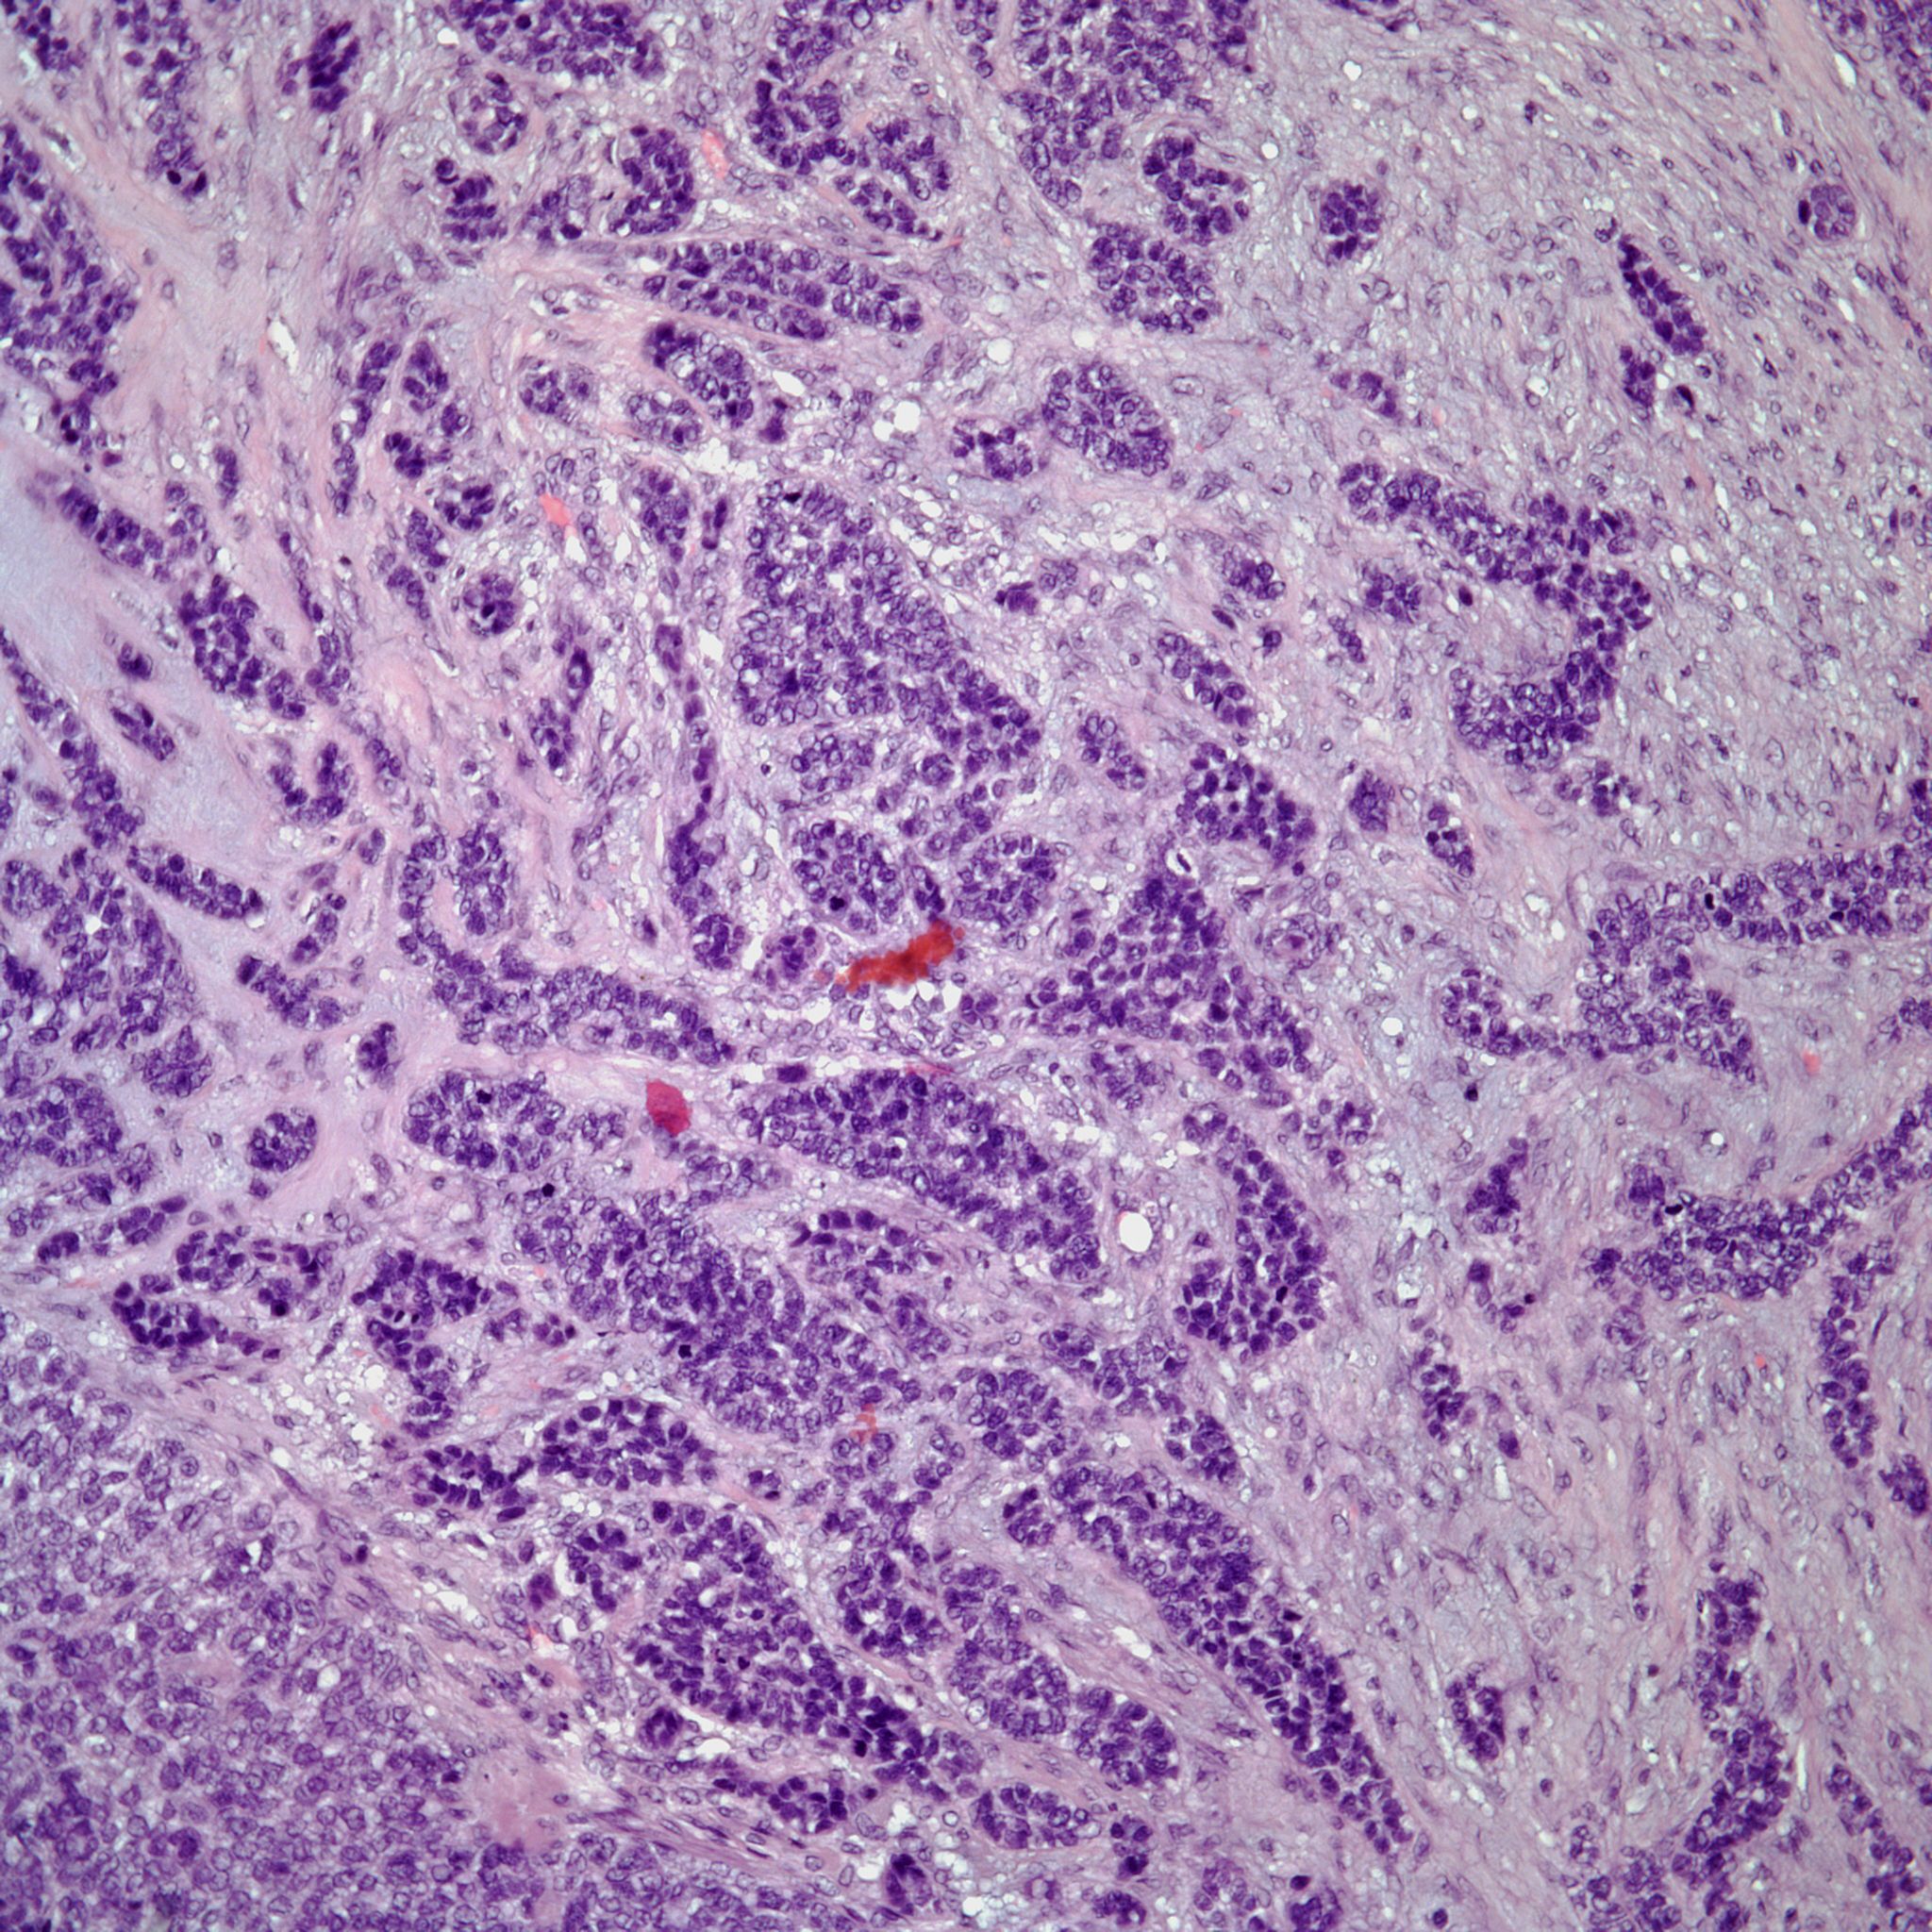

A 52-year-old woman presents with nasal congestion and an intranasal mass. What is your diagnosis?

Based on the image shown, what is your diagnosis?